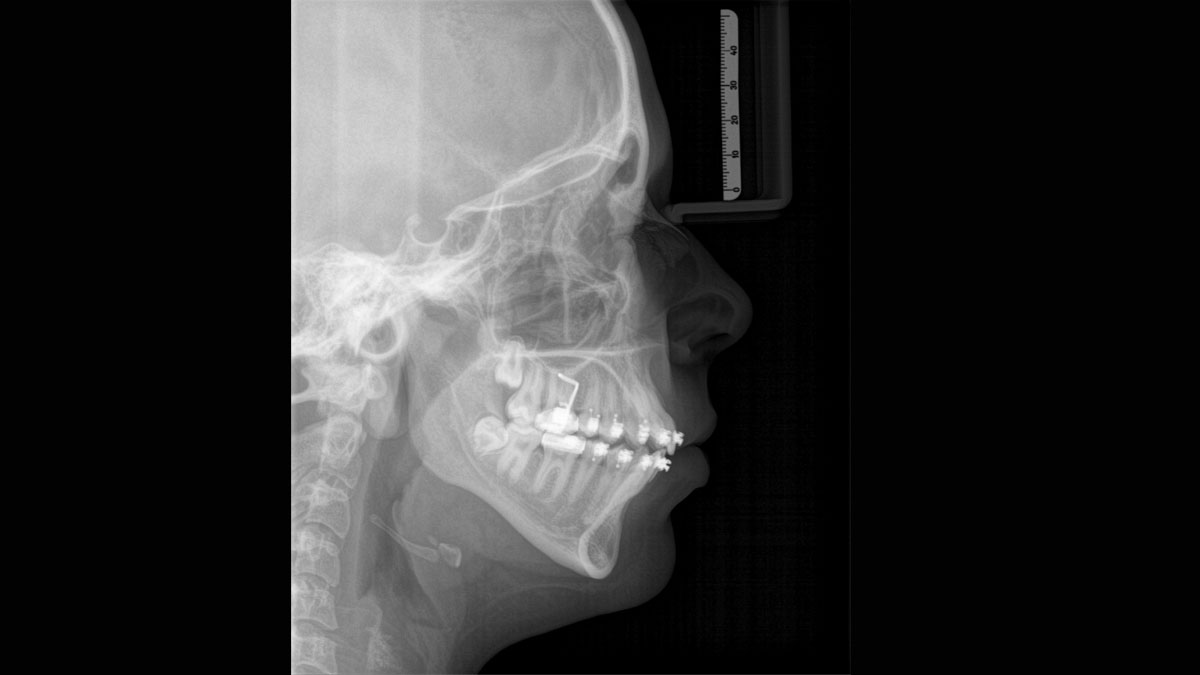

The high-quality 2D/3D X-ray device with a comprehensive range of services for every practice. Whether as a pure 2D device or including a 3D module – the Orthophos S is a reliable partner and optimized for everyday tasks. Its CsI Plus sensor with autofocus function ensures clear images, even in anatomically difficult cases. The automatic patient positioning together with the patented occlusal bite block enables an easy and timesaving patient positioning. For use in orthodontics, the Orthophos S is also available with an optional ceph arm. And because future-proofing is important to Dentsply Sirona, the cephalometric arm can be retrofitted at any time.

The right focus is crucial for excellent panoramic radiographs. With the autofocus function you will automatically receive an image with the best possible sharpness in focus. The Orthophos S creates several thousand individual images in one revolution and automatically recognizes the areas in which the jaw is optimally positioned. A sharp panoramic image is created from the individual projections – without any manual intermediate steps.